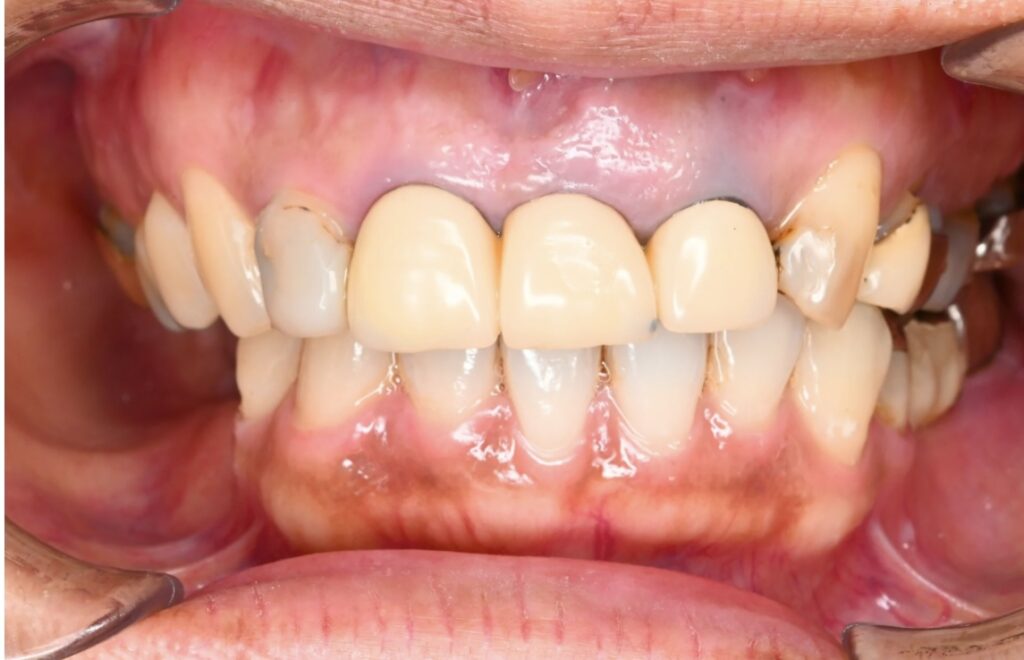

症例写真

口腔内の状況

⑦インプラントの上部構造と上の前歯にCAD/CAMによる白い歯を装着